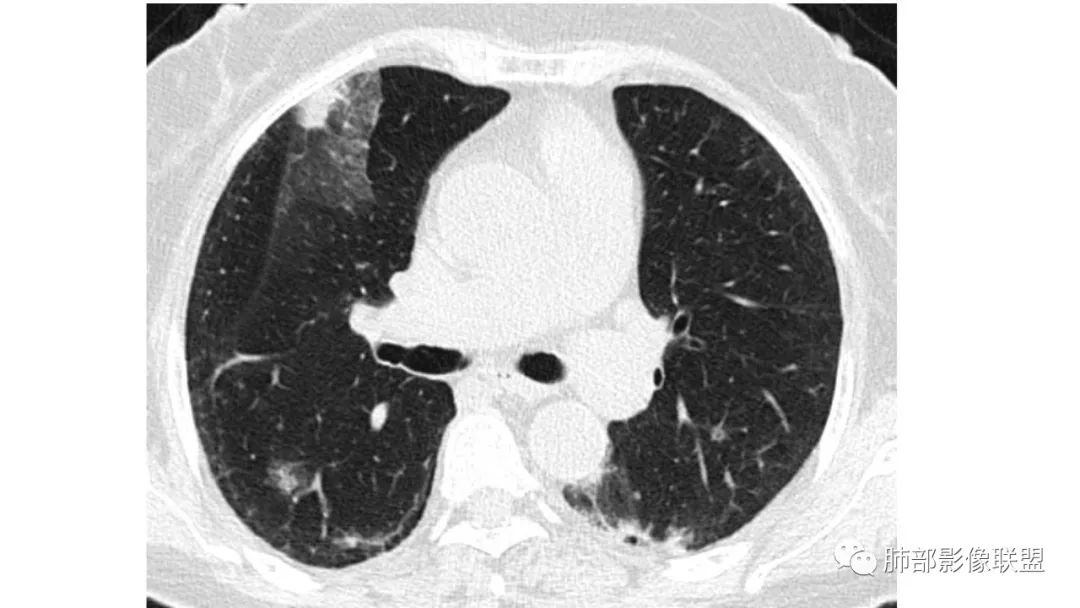

二、肺炎型

2、病灶常有一个主病灶,常位于下肺。后沿气道播散为多发病灶。

3、重力作用,叠瓦征。近叶间裂因重力效应,呈膨隆改变。

4、增强后不均匀强化,存在低强化区呈弱强化或无强化,因此可见“血管造影征。”血管毛糙与肺炎有统计学差异。

5、支气管粗细不均,呈“枯树枝征”,但与肺炎这一点鉴别不具有统计学差异。可发生支气管扩张

6、空腔形成,部分蜂窝状改变。

8、斑片常伴有结节,边缘清楚GGO或欠清楚。